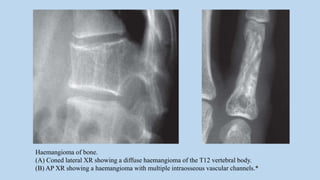

Haemangioma of bone.

(A) Axial CT showing a vertebral body haemangioma with fatty matrix and thickened primary

trabeculae.

(B) Sagittal T1WI showing a haemangioma of L5 with high SI due to fat.

(C) Axial T2WI showing a vertebral haemangioma in the right side of L2.*

(A) Coned lateral XR showing a diffuse haemangioma of the T12 vertebral body.

(B) AP XR showing a haemangioma with multiple intraosseous vascular channels.*

• 101.

Haemangioma of bone. (A)Coned lateral XR showing a diffuse haemangioma of the T12 vertebral body. (B) AP XR showing a haemangioma with multiple intraosseous vascular channels.*